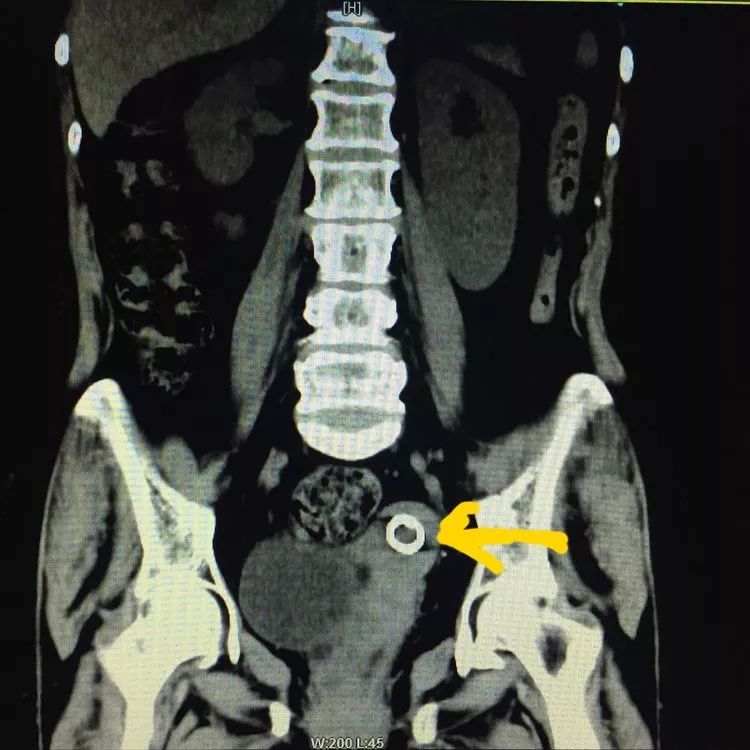

下面图中黄色箭头所指均为节育环的位置

近日,我院妇科接诊了一例困难型取环患者。患者蔚女士,年龄65岁,带环40余年,绝经期20年,近4年来无诱因出现下腹部胀痛,时轻时重,2年前曾在私人诊所取环,结果取出失败。现为求取环,患者及家属经过谨慎考虑,来我院。入院后妇科彩超提示:子宫萎缩,宫腔可见“O”形环回声,位置正常。马辉平主任考虑到患者绝经20年,子宫萎缩,曾经有过取环失败史,入院后经过各项详细检查排除,排除手术禁忌证,马辉平主任准备为其行宫腔镜下取环术,令人惊讶的是宫腔镜下居然没有见到节育环,却发现了个一个3✖️2.5厘米粘膜下肌瘤,蒂部来源于子宫前壁。马主任考虑节育器移位了,到底移位到了哪里呢?子宫肌层、盆腔、腹腔、膀胱等,这些部位的可能性都很大。为了进一步明确节育环移位的部位,又进行了透视及CT检查,均显示节育环在子宫内。